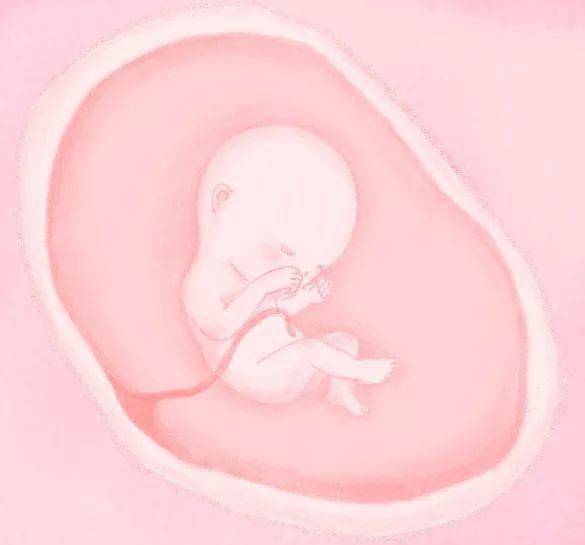

▲ 孕 4 月

胎儿的内脏器官几乎发育完全,脸上长出胎毛,胎盘形成,开始迅速成长,骨骼和肌肉发达,手指纹和脚趾纹形成,宝宝胎心率最快的时期, 性别可以完全区分了,腿长超过胳膊,手脚开始活动,但是妈妈还是感觉不到。